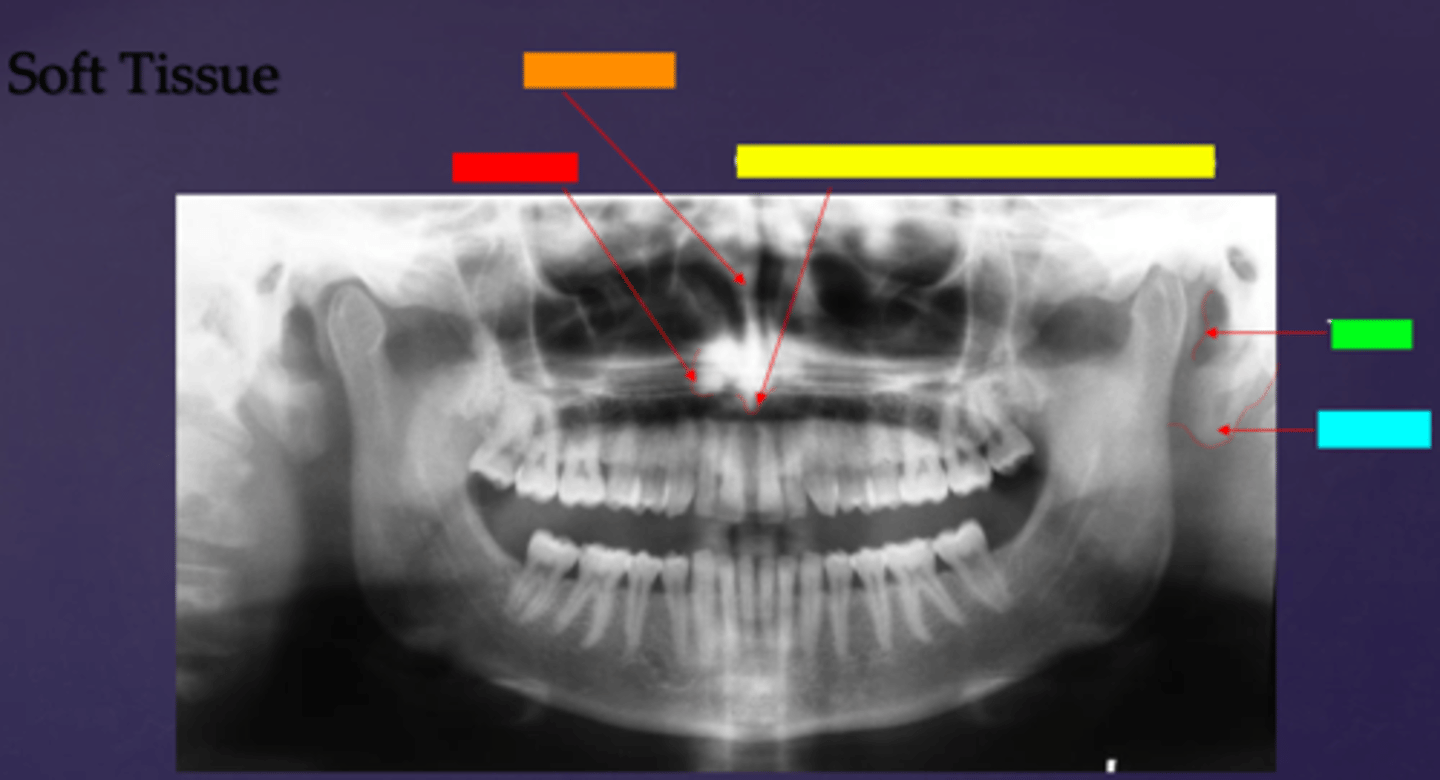

ID the soft tissue anatomy indicated by the arrow pointing from the red box:

posterior pharyngeal wall

ID the soft tissue anatomy indicated by the arrow pointing from the orange box:

soft palate

ID the soft tissue anatomy indicated by the arrow pointing from the yellow box:

dorsal surface of tongue

ID the soft tissue anatomy indicated by the arrow pointing from the green box:

middle nasal meatus

ID the soft tissue anatomy indicated by the arrow pointing from the light blue box:

inferior nasal meatus